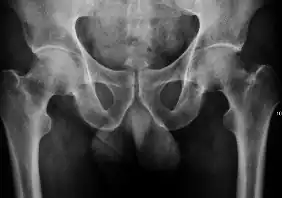

Plain radiography allows us to categorize the hip as normal or dysplastic or with impingement signs (pincer, cam, or a combination of both). Besides these, pathologic processes like osteoarthritis, inflammatory diseases, infection, or tumors can also be identified (Figure 1).[1]

Figure 1.

-

Radiography in normal hip -

X-ray in pincer impingement type of hip dysplasia -

X-ray of cam -

Hip in osteoarthritis -

Septic arthritis